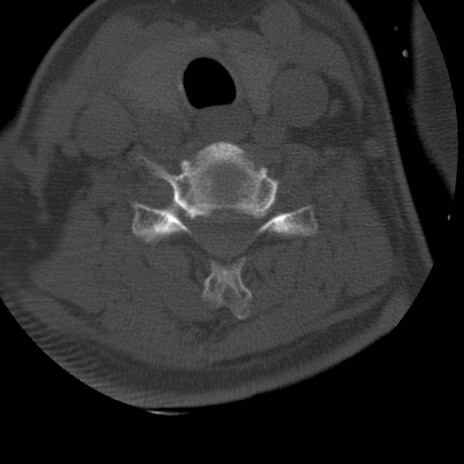

症例50 頚椎CT(横断像)

矢状断像